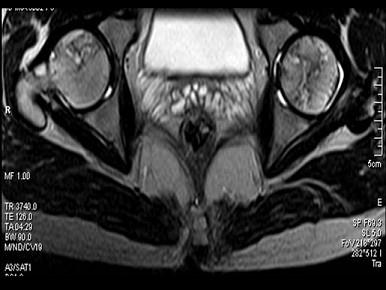

问题 患者,男,24岁,曾有外伤史,两侧髋部疼痛不适数月,请结合所提供的图像,选择最佳答案 ( )

选项 A、化脓性骨关节炎 B、类风湿关节炎两侧 C、髋关节退行性变 D、未见异常 E、股骨头无菌性坏死

答案 E